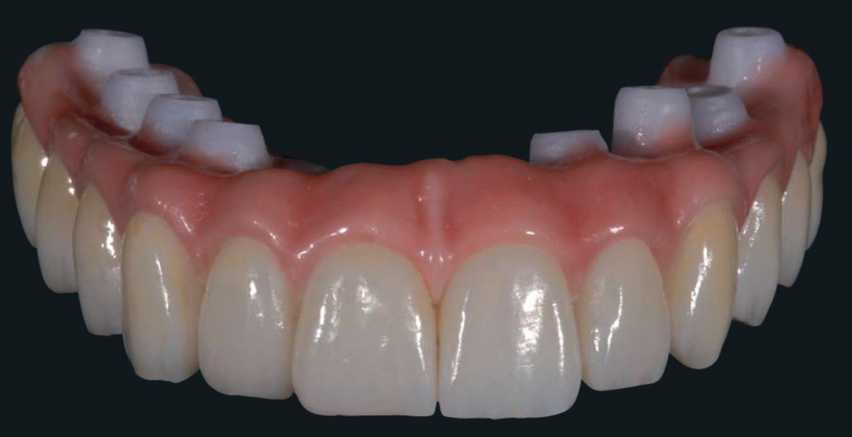

Plan D Fixed bridge that cannot be removed by yourself (the dentist can do so if required to adjust or inspect the implants).

Certainly one advantage of the removable solution is that you can remove it to clean the teeth. The main advantage of the fixed solution is that it is fixed! You will have to clean the inside, the outside and we will show you have to do this simply with electric toothbrush and special “under-bar” cleaning brush.